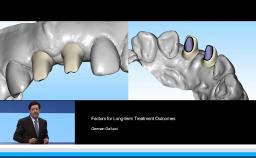

In step with the desire for rapid implant treatments, the demands for an esthetic outcome have also grown. In their lecture, Dean Morton and Waldemar Polido elaborate on how to address today’s esthetic demands, and how to prevent and treat esthetic failures. Viewers will also learn how to recognize situations where an elevated risk to an esthetic outcome exists.

- identify and discuss factors that influence esthetic outcomes

- recognize clinical conditions and treatment decisions where an elevated risk to an esthetic outcome exists

- explain procedures that may prevent esthetic failures

- describe procedures that can be used to treat esthetic failures